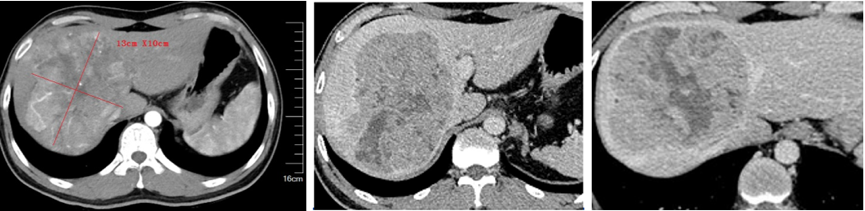

2020年10月30日上腹部CT平扫 增强检查,考虑肝右叶巨块型肝癌(13cm× 10cm),伴门脉右支部分分支癌栓形成(图1)。

图1.2020年10月30日上腹部CT